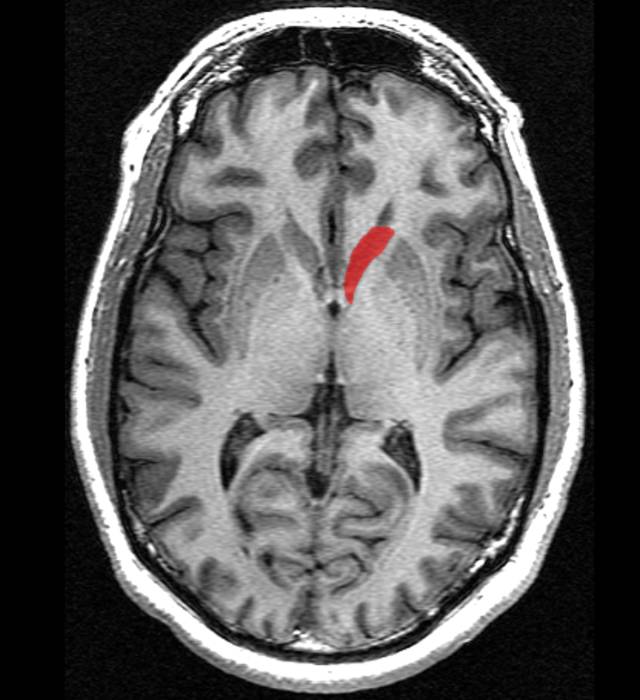

图 | 海马体

人脑中的海马体(Hippocampus)主要负责定向功能(又称“空间记忆”)和长期记忆(又称“情节记忆”)。

空间记忆十分强大的人,比如大城市里的出租车司机的海马体通常会比较发达。之前的一项伦敦出租车司机研究证明了这一点。而发达的海马体含有更多灰质,通常意味着一个更健康的大脑。